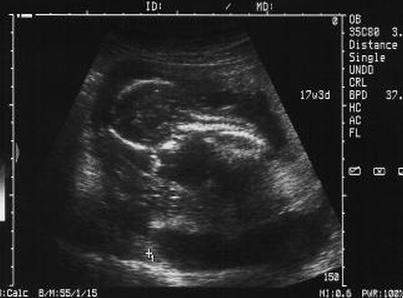

Эмбрион сейчас быстро развивается и к концу этой недели действительно начнет немного походить на человека. Беременность, как правило, определяется как по анализам мочи и крови, так и по сонограмме. К концу этих недель ваш эмбрион: